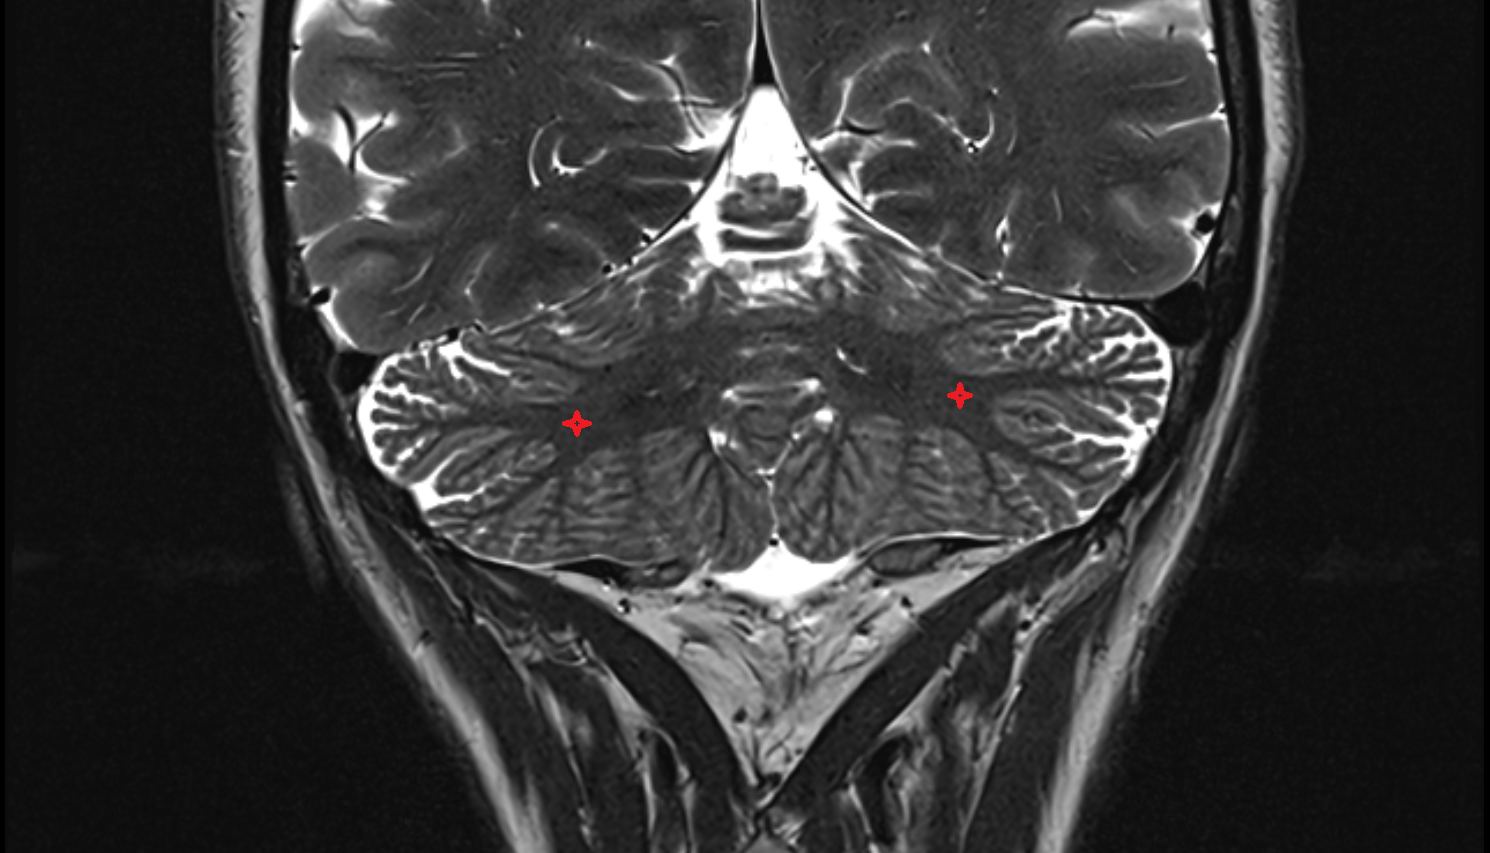

- Cerebellum

- Cerebellar tonsil (H IX)

- Crus I of ansiform lobule of cerebellum

- Crus II of ansiform lobule of cerebellum

- Paramedian lobule (HVII) of cerebellum

- Simple lobule (HVI) of cerebellum

- Biventral lobule (HVIII) of cerebellum

- Central lobule (II & III) of Cerebellum

- Culmen (IV, V) of Cerebellum

- Declive (VI) of Cerebellum